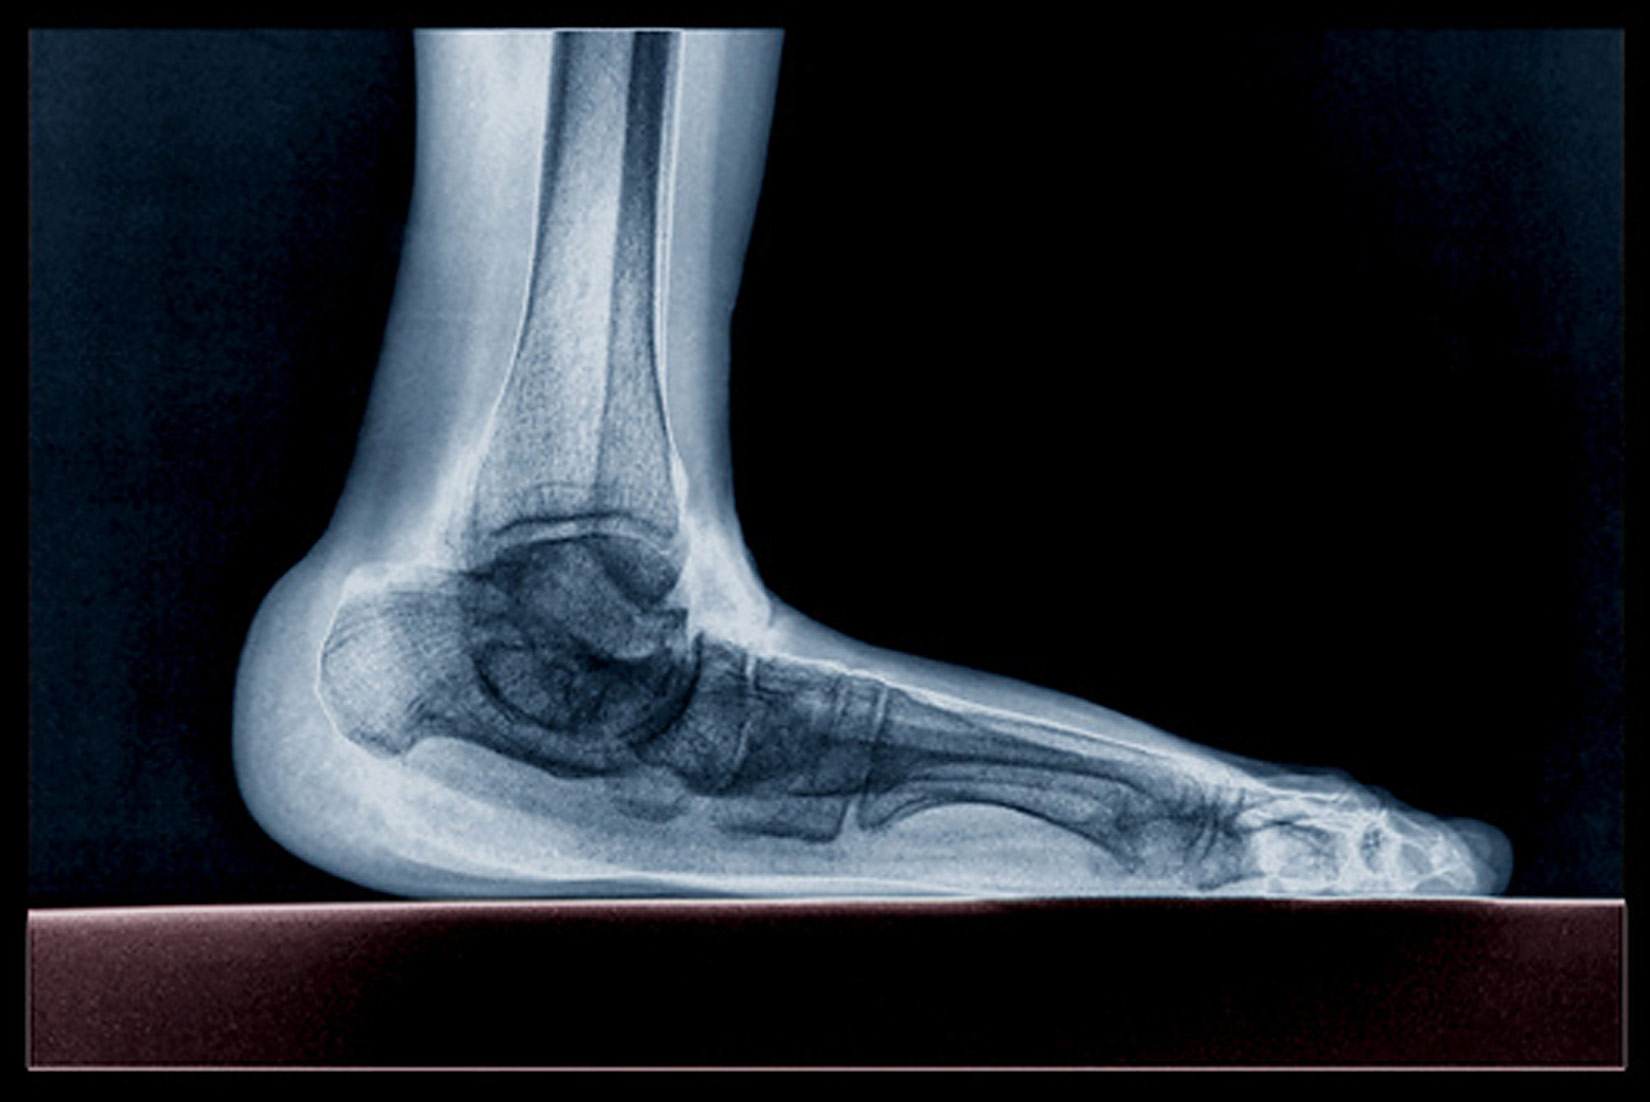

Jedna ili dvije točke

Stopala nose težinu cijeloga tijela.

- Proučite prikaz raspodjele težine na kosti stopala.

- Koja je bitna razlika između normalnoga i spuštenoga stopala?

Osobe koje imaju spušteno stopalo, trebaju vježbati mišiće u području stopala.

Neke od vježbi koje se preporučuju jest bosonogo hodanje po neravnome terenu, npr. šljunku ili plaži.